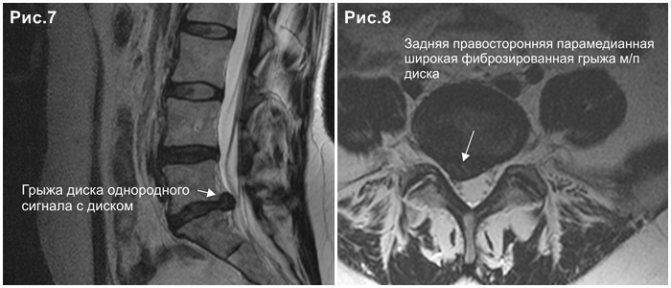

КТ-протрузии дисков: Визуализация и классификация

Раздел: Необычные решения